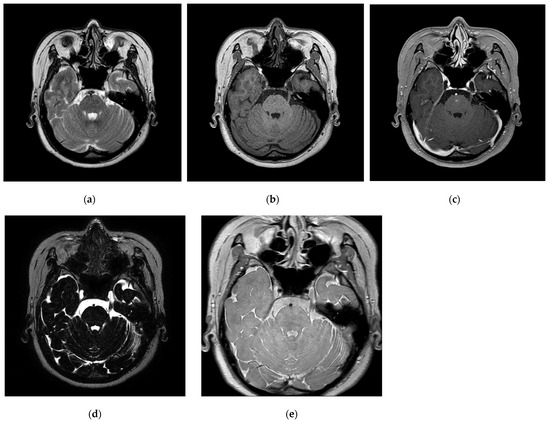

3.1. Improving the Image Quality of the Trigeminal Nerve